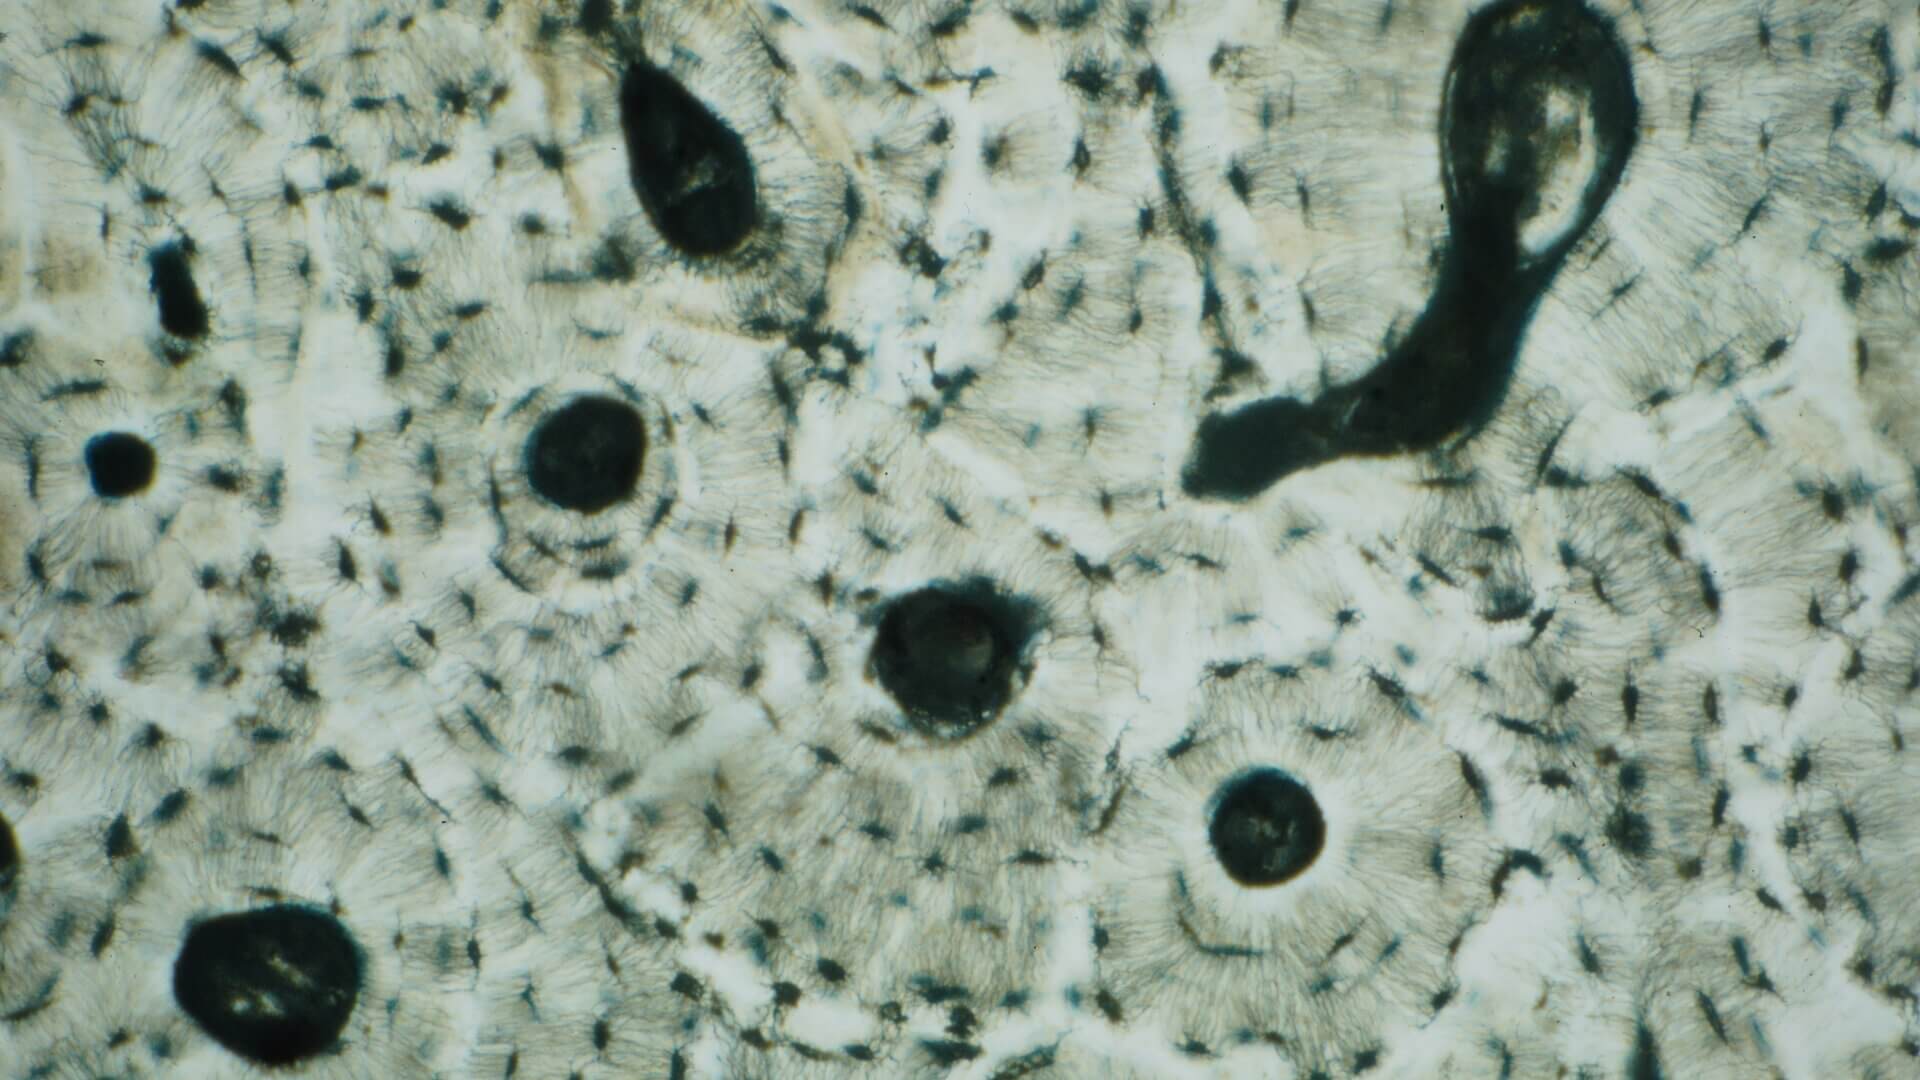

Histologisches Bild des Lamellenknochens: Rundlich angeordnet liegen die Osteone mit den Osteozyten (klein, schwarz). Mittig in einem Osteon liegt ein Havers-Kanal (rund, schwarz). Rechts oben entspringt ein Volkmann-Kanal aus einem Havers-Kanal. Schaltlamellen sind ebenfalls angeschnitten.